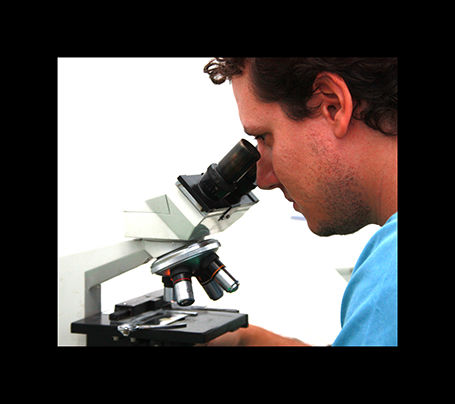

análisis clínicos

En clinican contamos con un laboratorio donde podemos realizar análisis de sangre, orina…